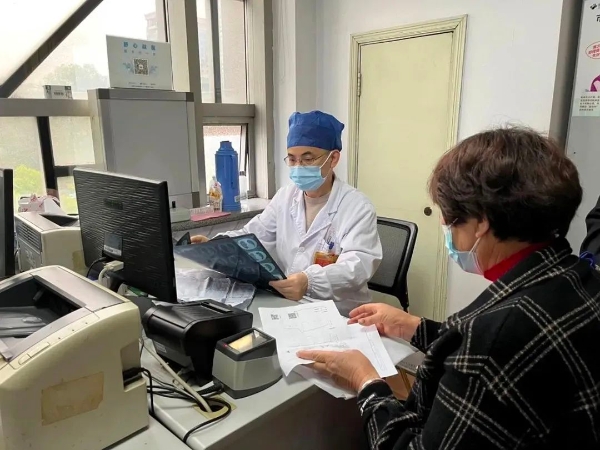

冷报浪主任医师在门诊

接诊的呼吸内科主任冷报浪主任医师了解到她口服速福达抗流感病毒后仍反复发热,并咳出黄色浓痰后,立即安排了相关检查。